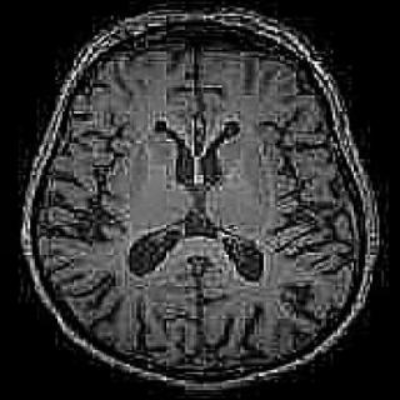

这是一张脑部横轴位MRI图像,呈现典型的T1加权像特征。图像中可见大脑皮层呈灰白色,白质区域为稍低信号,脑沟、脑回结构清晰可辨;中线处可见对称的侧脑室体部,其内脑脊液呈低信号,形态规则且无扩张或变形迹象;双侧基底节区及丘脑结构显示正常,未发现异常高信号或占位性病变。从任务目标"基于深度学习的脑肿瘤检测与定位"来看,该图像是模型训练与验证的关键数据载体——通过提取图像中脑组织的纹理、信号强度分布、解剖结构边界等特征,深度学习模型可学习区分正常脑组织与肿瘤组织的模式,进而实现对肿瘤的自动检测与空间定位。图像中若存在肿瘤,通常会表现为异常信号灶(如T1低信号、T2高信号的占位),但此图暂未显示明显肿瘤征象,可作为正常样本用于模型对非肿瘤区域的识别训练,也可作为对照帮助模型明确肿瘤区域的特征差异。

这是一张大脑的轴位MRI影像,呈现典型的T1加权像特征。图像中可见左右对称的大脑半球结构,中央为纵裂分隔两侧脑组织,中间可见呈低信号形态的侧脑室体部,其轮廓清晰且位置居中。大脑皮层表面可见明显的脑沟回结构,灰白质对比度良好,白质区域信号相对较高,灰质区域信号稍低。从整体来看,脑实质内未发现明显异常高信号或低信号占位性病变,各解剖结构在空间分布上保持正常形态。结合"基于深度学习的脑肿瘤检测与定位"这一任务目标,该图像是深度学习模型训练与验证的关键数据载体——通过提取此类影像中肿瘤相关的视觉特征(如异常信号强度、边界形态、位置分布等),构建算法可实现对脑肿瘤的自动化识别与精准定位,为临床诊断提供技术支持。

这是一张轴位脑部MRI图像,呈现大脑横断面的解剖结构。图像中可见左右对称的脑沟回、侧脑室(呈"八"字形分布于中线两侧)、第三脑室(位于双侧侧脑室下方)及部分脑干结构,灰白质对比清晰,脑实质信号均匀,未发现明显异常占位性病变或形态学改变。从任务目标来看,该图像是深度学习模型训练与测试的核心数据载体——模型需通过分析此类图像中正常脑组织的纹理、形态及信号特征,建立基准认知;同时,若存在肿瘤时,需识别肿瘤在T1加权像下的异常高/低信号、边界模糊度、周围组织受压变形等特征。此图虽为正常脑部影像,但能为模型提供"无肿瘤"类别的样本支持,帮助模型区分健康与病变区域的差异,是实现精准脑肿瘤检测与定位的基础数据之一。